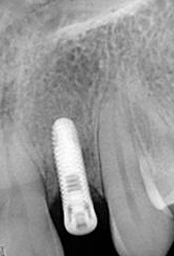

X-ray of Implant

Single Tooth Implant

X-ray of Implant + Abutment

X-ray of Implant +

Abutment + Prosthesis

Placement of Bone Grafting

Abutment+ Prosthesis